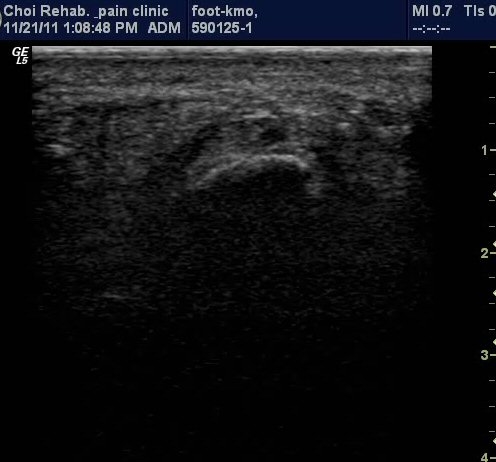

Ⱦ´Ü¸é°Ë»ç¿¡¼­µµ Á·Àú±Ù¸·ÀÇ Àú¿¡ÄÚ ºÎÁ¾ÀÌ ¶Ñ·ÈÇÔ(±×¸² 3).